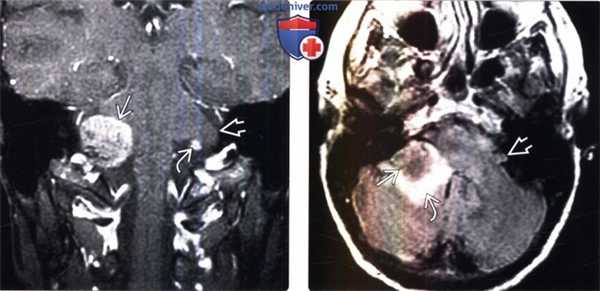

(Слева) МРТ, постконтрастное Т1-ВИ, аксиальный срез: метастазы рака легкого в твердую мозговую оболочку в области ММУ. Необходимо различать контрастируемую утолщенную твердую мозговую оболочку от нормального участка контрастирования сигмовидного синуса. При исследовании СМЖ были выявлены злокачественные клетки.

(Справа) МРТ, постконтрастное Т1-ВИ, режим подавления сигнала от жира, аксиальный срез: в правом ВСПВ определяется контрастируемый метастаз, распространяющийся через канал улиткового нерва и стержень улитки в перепончатый лабиринт.

(Слева) МРТ, постконтрастное Т1-ВИ, корональный срез: в клочке правого полушария мозжечка определяется контрастируемый метастаз карциномы молочной железы. Обратите внимание на нормальный клочок и сосудистое сплетение цистерны

(Справа) МРТ, FLAIR, аксиальный срез: у этого же пациента определяется, что объемное образование несколько гипоинтенсивнее прилегающего серого вещества мозга. Вазогенный отек вещества средней ножки и самого мозжечка визуализируется как гиперинтенсивная область. Левый клочок в норме.